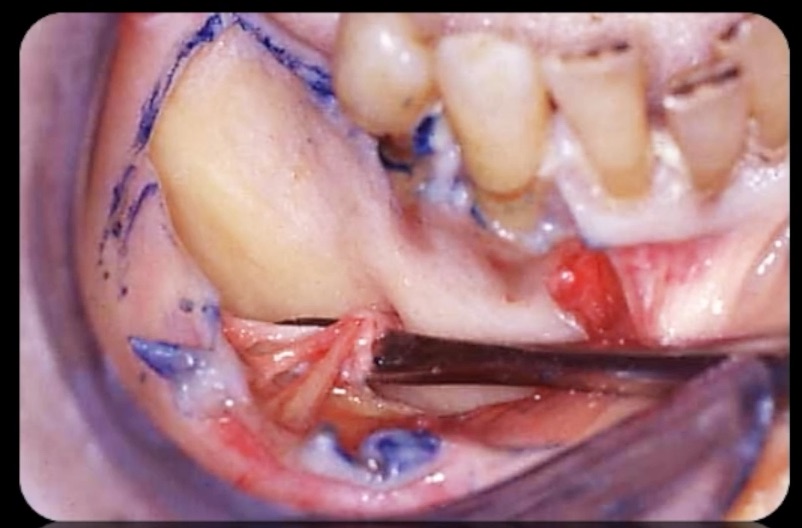

The management of the anterior open bite may be quite challenging and in some cases necessitates a multidisciplinary approach. We present here a patient suffering from an anterior open bite with an ankylosed central incisor due to previous trauma. The anterior open bite was corrected using conventional orthodontics and the ankylosed incisor was repositioned in the correct tri dimensional position using segmental osteotomy. The repositioned bone block needed 5 months of stabilization and the prosthetic rehabilitation of the anterior maxilla was completed using e-max crowns. At 24 months ,the result was stable with no relapse and an excellent pink and white esthetic score.